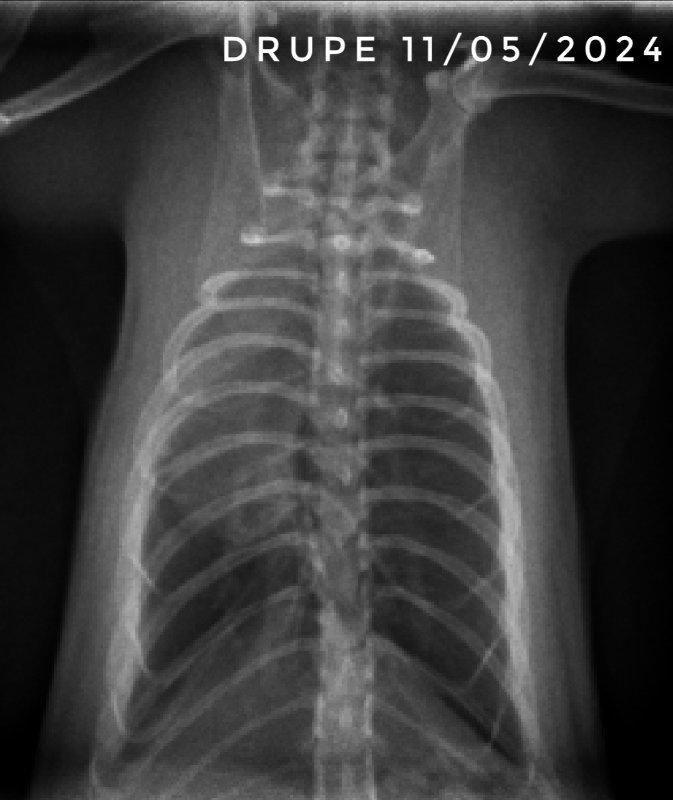

Et voici les dernières radios de Drupe. On est donc normalement sereins, les poumons ne sont pas parfaits, mais on est sûrement sur des cicatrices. Maintenant, il lui reste à passer l'étape de la castration et normalement ensuite il sera tranquille niveau soins vetos ^^

Chez les autres bébés qui ont survécut et qui ont arrêté les traitements en février, un seul a été provisoirement remis sous traitement, et c'est suite à des petits éternuements sur toute la troupe, qui n'ont pas commencés par lui, et il n'a pas été particulièrement touché. Ils ont tous des poids corrects pour des ratons de leur âge, sauf Drupe qui est plus petit mais il prend progressivement quand même.